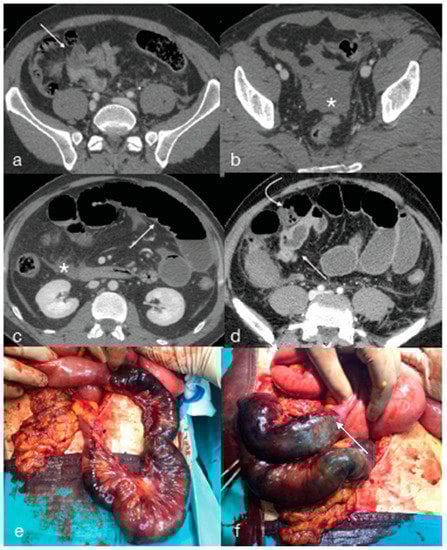

- Di Serafino, M.; Iacobellis, F.; Schillirò, M.L.; Ronza, R.; Verde, F.; Grimaldi, D.; Dell’Aversano Orabona, G.; Caruso, M.; Sabatino, V.; Rinaldo, C.; et al. The Technique and Advantages of Contrast-Enhanced Ultrasound in the Diagnosis and Follow-Up of Traumatic Abdomen Solid Organ Injuries. Diagnostics 2022, 12, 435. [Google Scholar] [CrossRef] [PubMed]